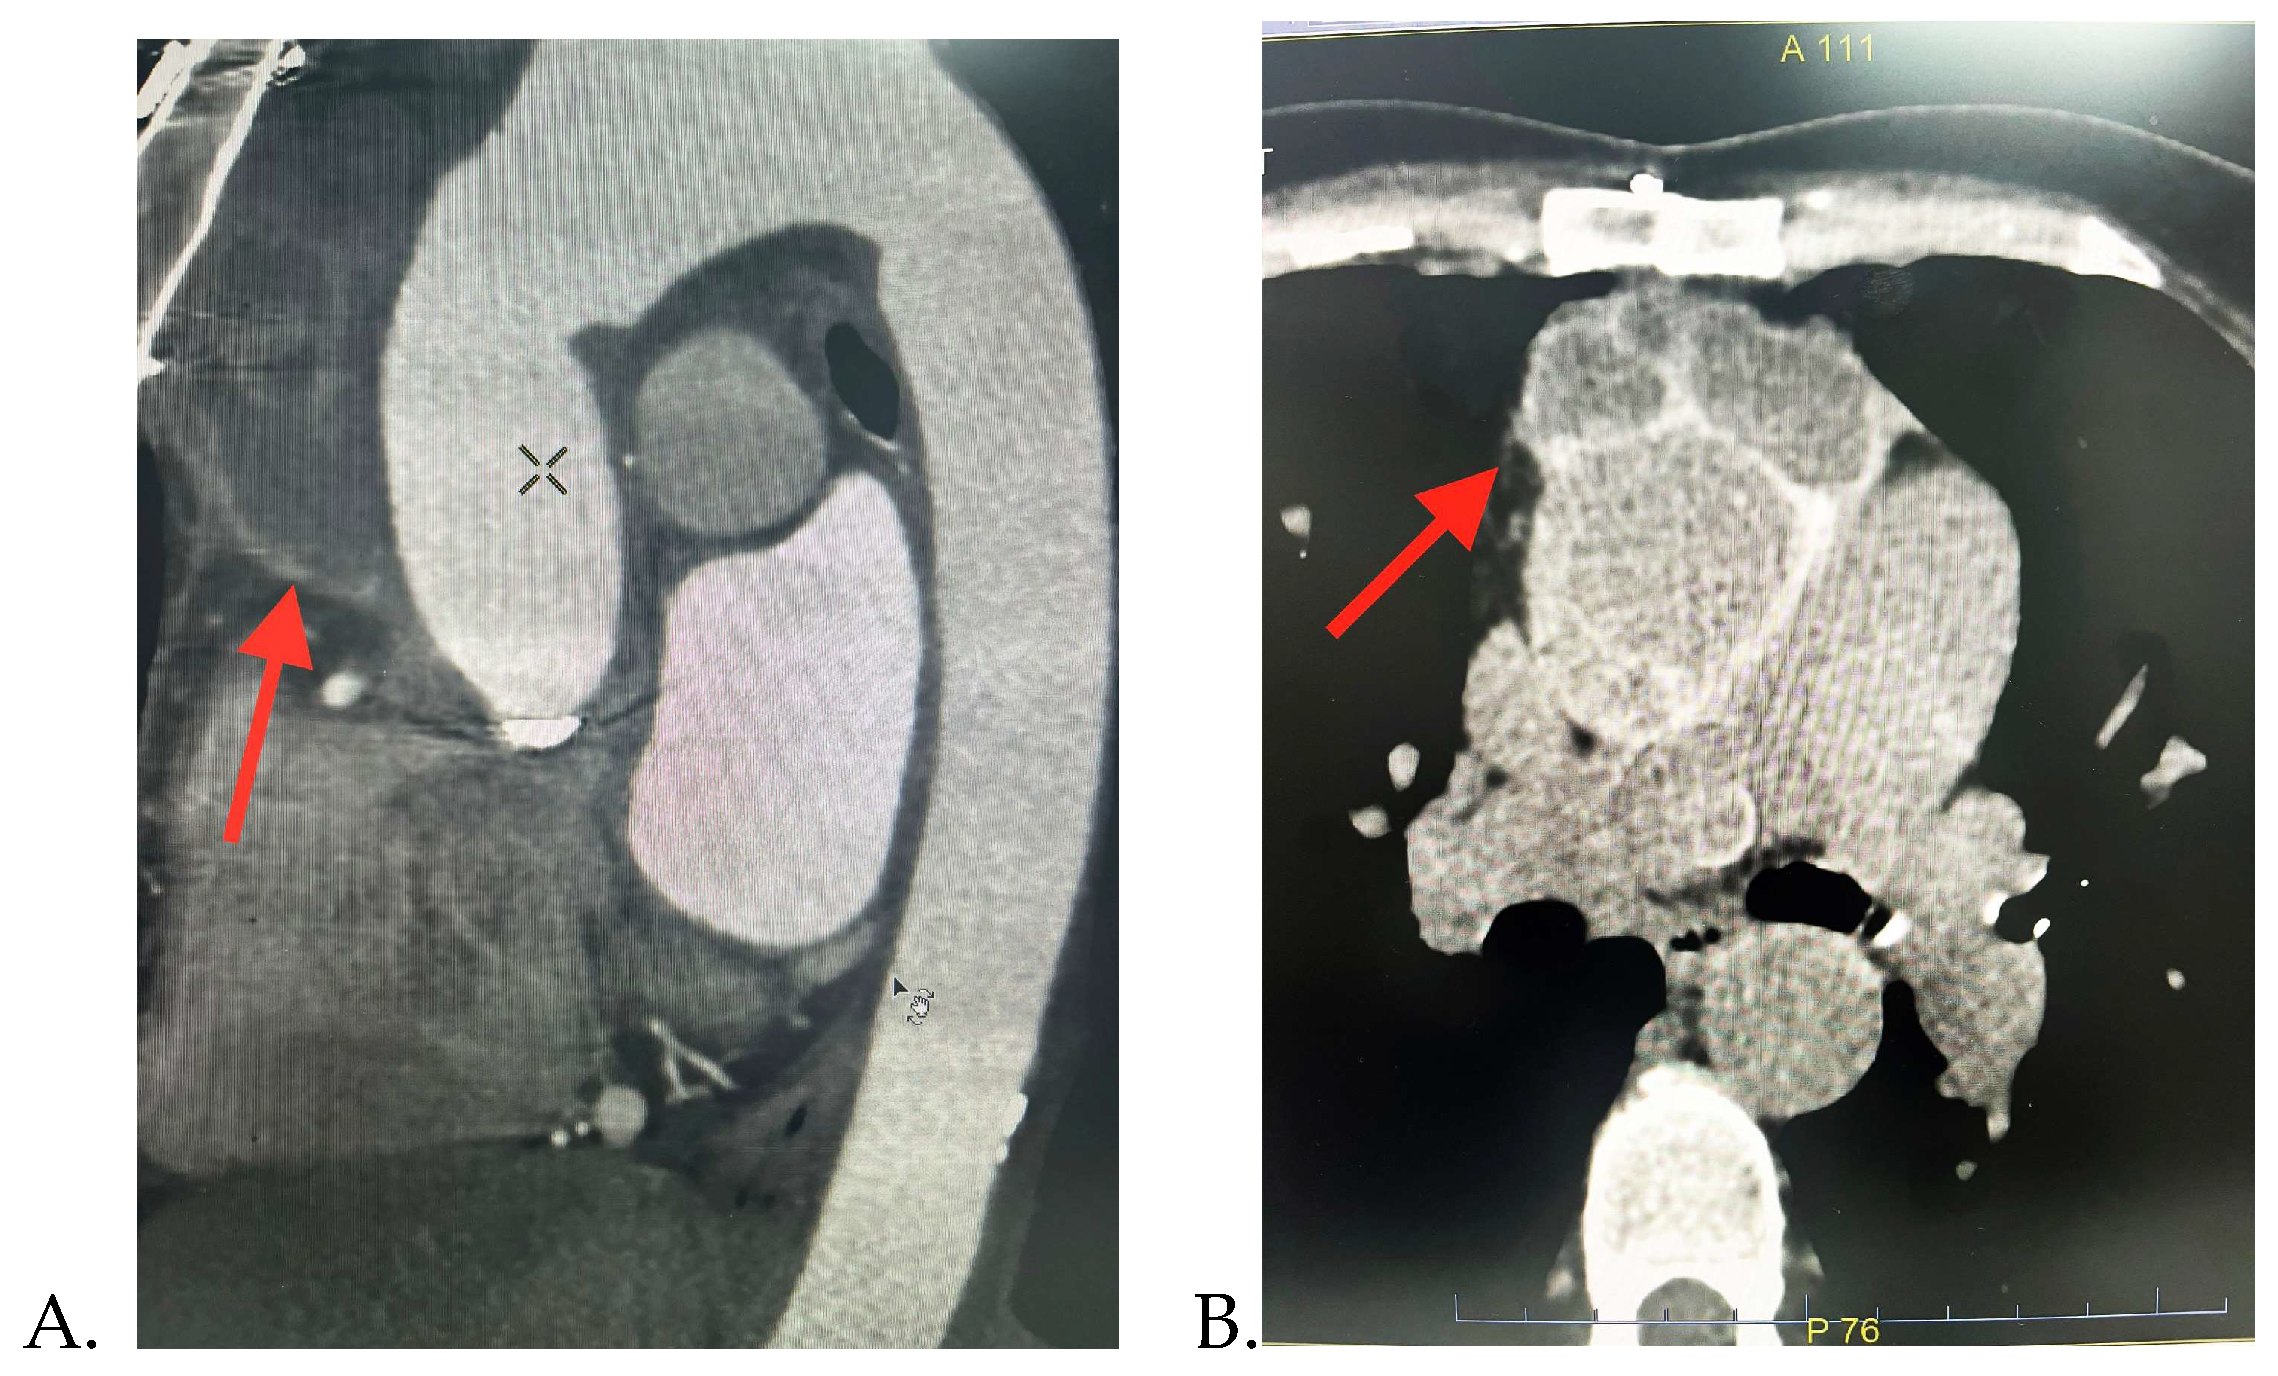

Alternatively, due to the echocardiographic images revealing a significant peri-aortic mass, it was decided to perform further investigations. The thorax CT scan detected a multiloculated right semi-circumferential fluid accumulation with iodophilic walls that extends from the level of the aortic valve along the aortic prosthesis to the anterior mediastinum, suggesting a peri-aortic abscess. Pericardial and pleural fluid collection and mediastinal adenopathies were also found.

Figure 2. Thorax CT-scan images showing the periaortic fluid accumulation (red arrow): A. Sagittal; and B. Axial section.